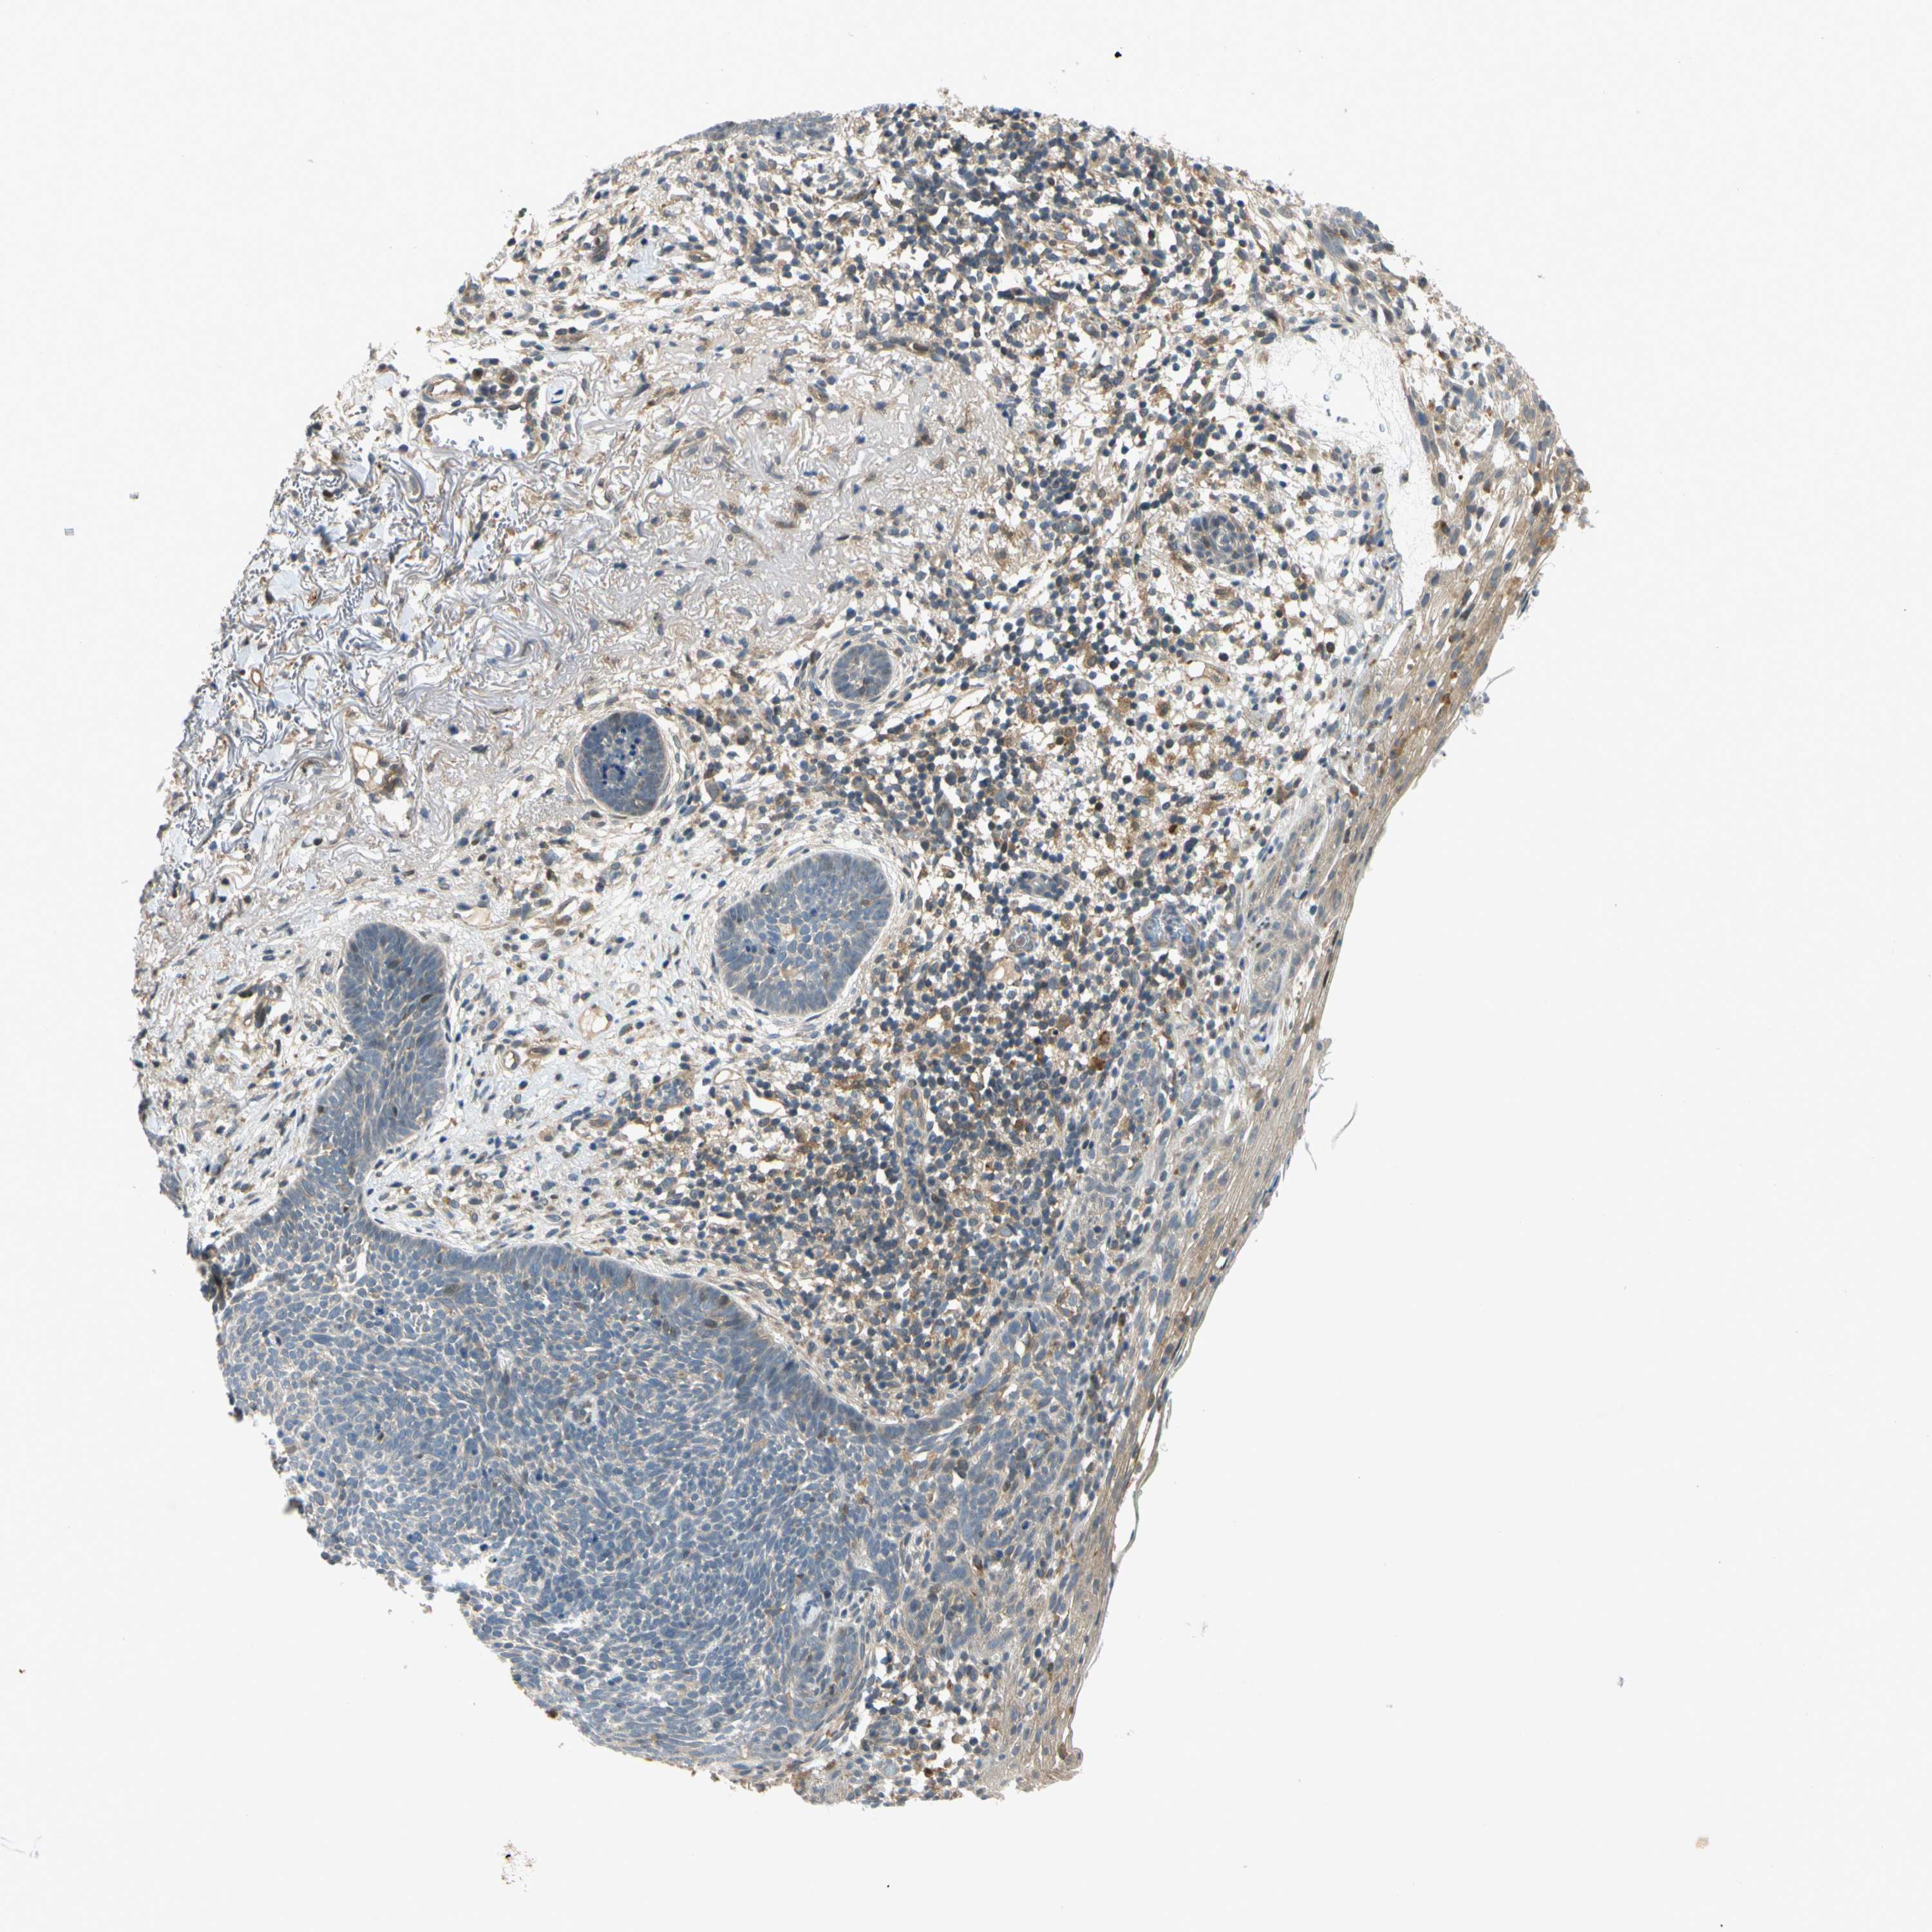

CANCER SKIN CANCER Show tissue menu

Basal cell and squamous cell cancer

SKIN CANCER - Protein expressioni

A mouse-over function shows sample information and annotation data. Click on an image to view it in a full screen mode. Samples can be filtered based on level of antibody staining by selecting one or several of the following categories: high, medium, low and not detected. The assay and annotation is described here.

Each image is clickable and will lead to virtual microscopy that enables deeper exploration of all samples and also displays staining intensity scores, fraction scores and subcellular localization as well as patient and tissue information for each sample.

Antibody HPA008812

Staining

High

Medium

Low

Not detected

Intensity

Strong

Moderate

Weak

Negative

Quantity

>75%

75%-25%

<25%

None

Location

Nuclear

Cytoplasmic/membranous

Cytoplasmic/membranous,nuclear

Squamous cell carcinoma, NOS

Basal cell carcinoma